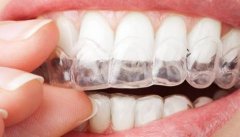

前牙开颌是解决牙齿畸形的最理想方法,通过医学的方法,用矫正器使牙齿进行...【详细】